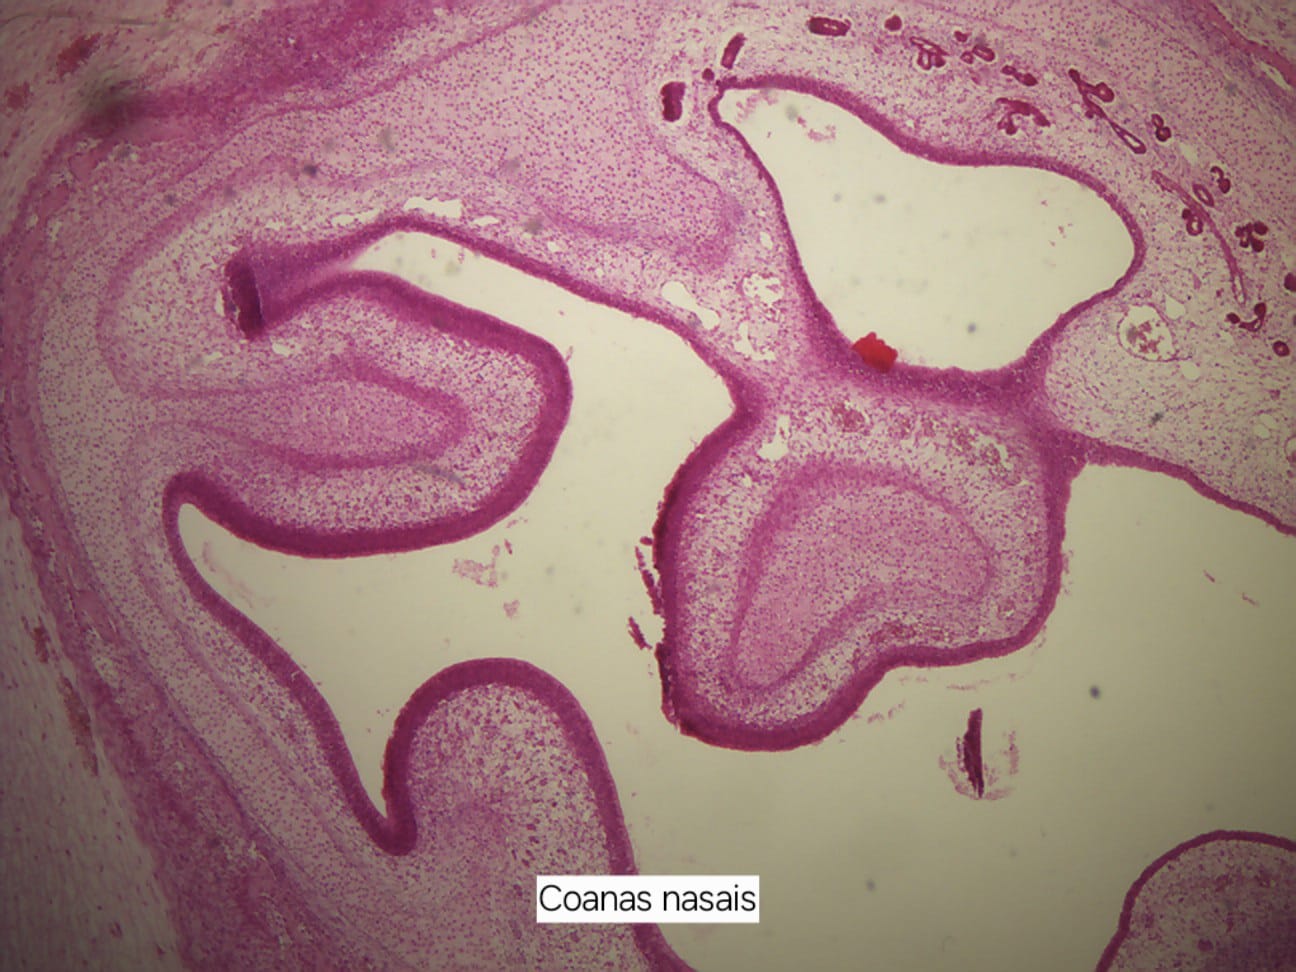

Imagens Embriologia da Face